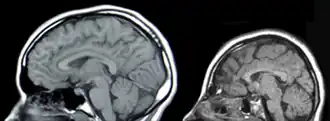

![]() Imagine IRM a craniului unei persoane sănătoase (stânga) și a unui pacient cu microcefalie (dreapta) | |